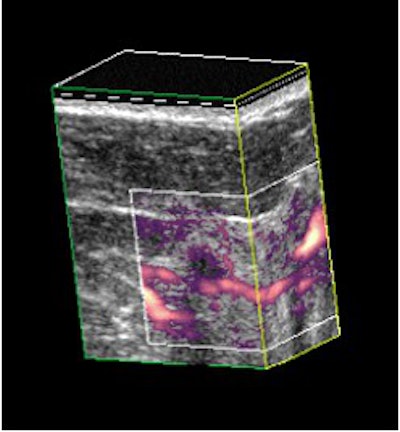

Ductal carcinoma in situ (arrows) shown in 3-D power Doppler before (above) and after (below) injection of 1 ml of Optison. Images courtesy of Flemming Forsberg, Ph.D.